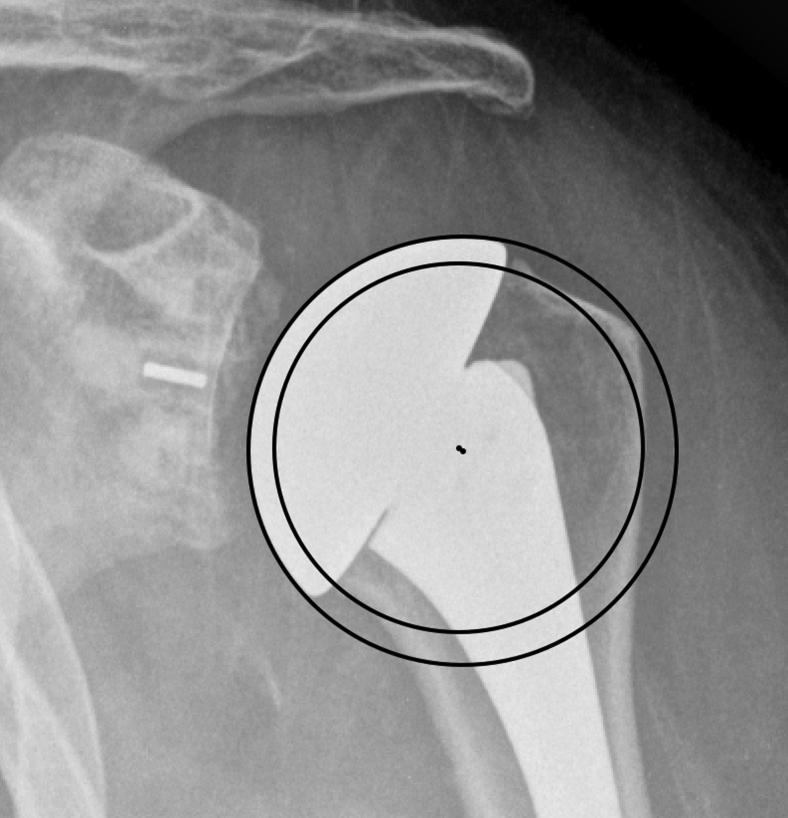

Fifty-five consecutive anatomic total shoulder arthroplasties performed using extra-short humeral heads were retrospectively reviewed and compared with age- and sex-matched controls receiving standard short heads. A total of 110 postoperative radiographs were analyzed using the Iannotti's perfect circle method to compare the prosthesis' center of rotation (COR) with the native humeral head COR. A difference in the COR of >3.0 mm was considered malpositioned. Malpositioning medially was considered overstuffed, and malpositioning laterally was considered understuffed. The direction of displacement of malpositioned prostheses was categorized using a quadrant system. Furthermore, we used a novel method to evaluate medial and superior overstuffing by measuring the displacement between the anatomic and prosthetic head positions along perpendicular axes.

回顾性分析连续55例使用超短肱骨头进行的解剖型全肩关节置换术,并与接受标准短肱骨头的年龄和性别匹配的对照组进行比较。使用伊诺蒂(Iannotti)的完美圆方法分析总共110张术后X线片,以比较假体的旋转中心(COR)与天然肱骨头的COR。COR差异>3.0mm被认为是位置不当。向内侧的位置不当被认为是过度填充,向外侧的位置不当被认为是填充不足。使用象限系统对位置不当的假体的移位方向进行分类。此外,我们使用一种新方法,通过测量解剖头和假体头位置沿垂直轴的位移来评估内侧和上方的过度填充。